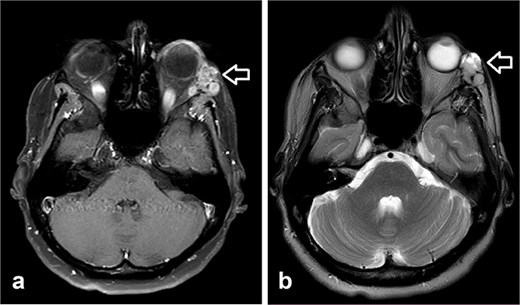

Orbit MRI showed a lobulated, well-defined lesion, hyperintense to intermediate on T2W (b) and hypointense on T1W (a) structures with cystic changes, measuring 2.3 × 1.9 cm and 2.6 × 1.6 cm, compared with the previous study, the lesions have increased in size.

MRI is the preferred modality to detect bony invasion and perineural spread. ACC usually appears as T1 isointense and T2 hyperintense with enhancement . Our patient's orbit MRI showed a lobulated, well-defined lesion, hyperintense to intermediate on T2W and hypointense on T1W structures with cystic changes.